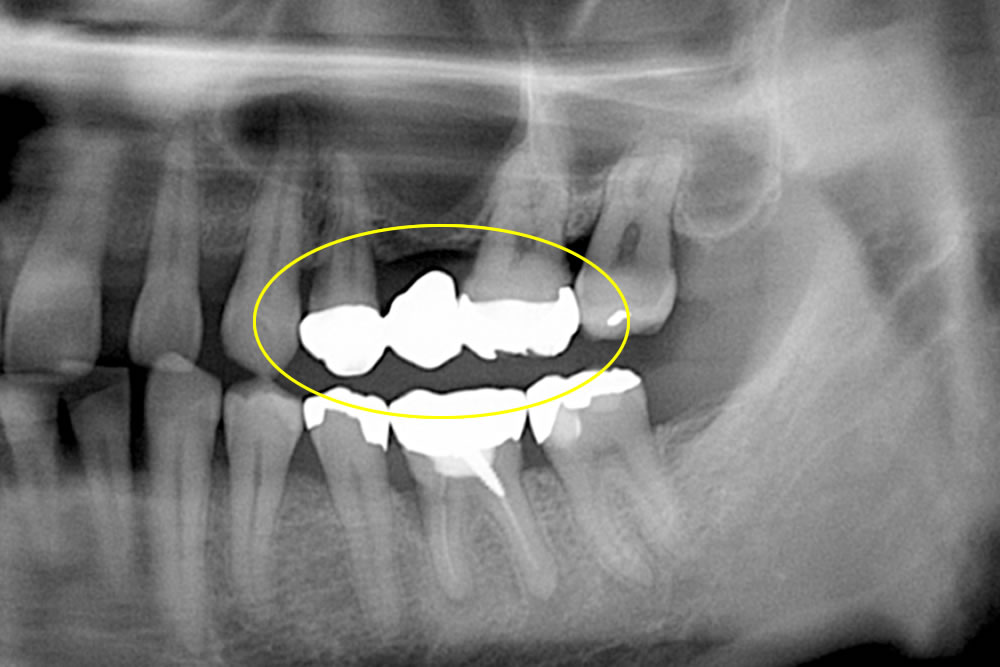

奥歯のブリッジを銀歯からジルコニアへ変更した症例

奥歯のブリッジを銀歯からジルコニアへ変更した症例 こちらの患者さまは、左上奥歯の銀歯のブリッジを白いものに変えたいとの事で来院されました。 真ん中の歯が無くなってから長年ブリッジで使用していたので、上の骨が殆どない状態に […]